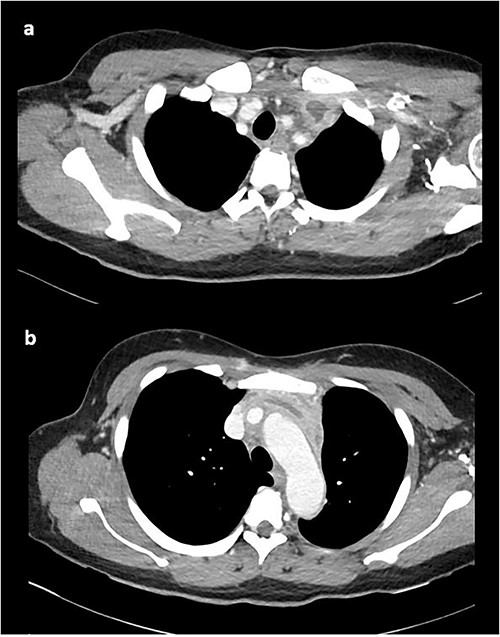

At this time, the mass was suspicious for a malignancy, possibly a thymoma, lymphoma or germ cell tumour. All serum tumour markers (AFP, CEA, CA19-9, CA125) were negative. FDG-PET demonstrated that the anterior mediastinal density had moderate FDG update and no other avid lesions elsewhere. After multidisciplinary discussion, the mediastinal density was thought to most likely represent left brachiocephalic venous thrombophlebitis. A dedicated computed tomography (CT) venogram was performed, demonstrating extensive UEDVT from the left internal jugular vein extending into the left brachiocephalic and subclavian veins, seen in Fig. 3.

CT venogram demonstrating UEDVT in left brachiocephalic vein in the (a) upper chest and (b) lower chest.